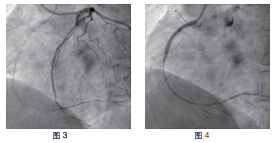

患者RCA为完全闭塞病变,用6F.EBU 3.5导引导管经股动脉对侧造影显示间隔支到RCA远端的侧枝循环,如正向无法开通右冠状动脉可改逆向开通。用JR6F-4导引导管两条pilot-50导引导丝在微导管支持下,用平行导丝技术通过闭塞病变(图3)。分别用Sprinter 1.5 mm×15 mm和2.5 mm×15 mm球囊扩张后RCA开口出现严重夹层,在RCA近端置入Partner 3.0 mm×36 mm支架(图4)。但支架远端仍有严重狭窄,IVUS证实RCA全程弥漫病变,用原2.5 mm球囊扩张后支架远端后,支架远端出现螺旋夹层。拟通过近端支架置入另一Partner 2.75 mm×36 mm支架,但支架无法通过近端支架,头端卡在第一个支架内,在反复用力推送过程中导引导管、导丝自RCA中脱出、将支架球囊弹出,支架球囊撤出体外后发现支架已脱落。透视RCA开口至桡动脉全程,及导引导管内,未发现脱落支架。迅速将原JR4导引导管到位,置BMW导丝到RCA远端,保证RCA开通(图5),IVUS证实导丝全程在真腔内。用原2.5 mm球囊扩张RCA远端以便器械通过(图6)。血管内超声检查提示RCA中段螺旋夹层,撕裂深及血管外膜(图7)。右冠近端支架膨胀、贴壁良好(图8)。将超声导管回撤至右冠状动脉开口处,可见脱落支架卡在右冠状动脉近端支架开口处(图9)。拟取出支架,为预防取出支架过程中RCA急性闭塞,在RCA远端置入BuMA 2.5 mm×30 mm和3.0 mm×30 mm支架,近端支架和原RCA开口处支架未连接(图10)。将Snare圈套器经原作为对侧造影的6F.EBU 3.5导引导管伸出(图11),调整位置,将脱落的支架套住。同时将RCA内的导丝保留,RCA近端支架内预置一3.0 mm×10 mm高压球囊,以保护在取出脱落支架时RCA开口处支架不受影响(图12)。在回撤圈套器时遇到较大阻力,反复推拉,在取出脱落支架的同时将置入RCA开口已释放的的Partner 3.0 mm×36 mm支架带出(图13~14)。RCA开口出现螺旋夹层,但未闭塞。立刻重新置入导丝,IVUS证实导丝在真腔内,在RCA近端分别置入BuMA3.0 mm×25 mm和3.5 mm×20 mm支架,RCA无残余狭窄,血流TIMI3级(图15)。